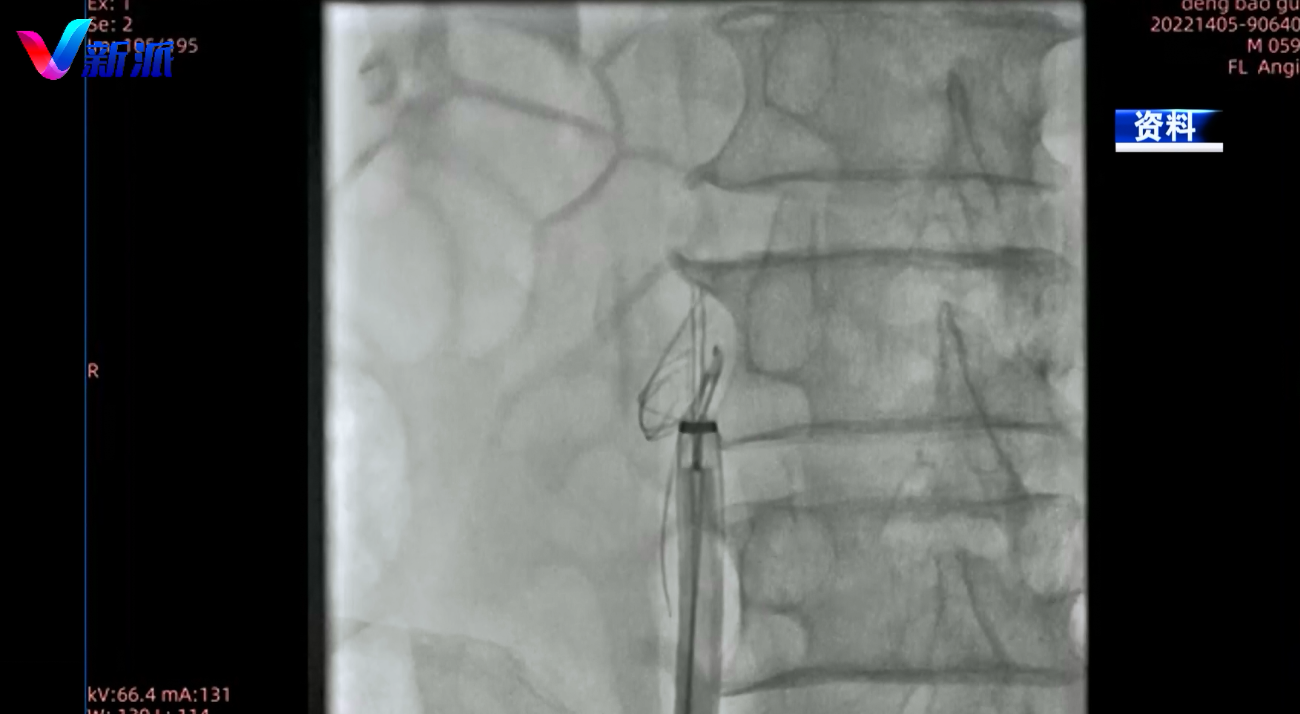

原来,邓先生体内的这个滤器原本应类似一个伞状,通过微创手术即可取出,可是经历多次手术后,滤器已经严重变形,国内众多三甲医院甚至只能考虑通过外科手术的方式开腹取滤器。近日,张希全教授团队通过微创的方式仅用半个小时便成功地将严重变形的滤器取出,长期压在邓先生心里的一块巨石也顺利清除。

潍医附院介入血管外科中心主任张希全教授介绍,这个滤网已经内膜增生 跟血管壁长到一块了,像剥鱼刺一样,要一点一点剥开,从血管壁上剥开,取出来。此独创的技术叫内膜剥离和loop技术,不像动脉一样,静脉壁薄、脆弱,容易穿破,需要医生功夫在手上。